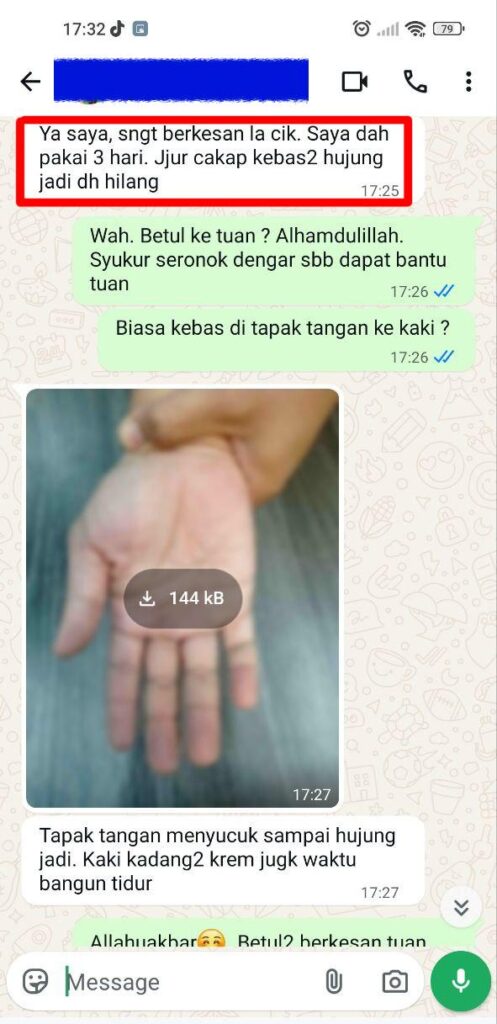

Individual results may vary, and testimonials are not claimed to represent typical results.

All testimonials are by real people, and may not reflect the typical purchaser’s experience, and are not intended to represent or guarantee that anyone will achieve the same or similar results.